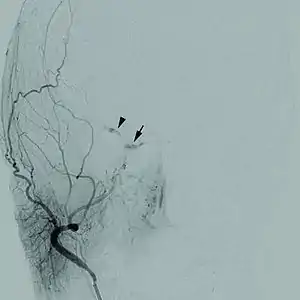

| رگنگاری مخ از فیستول کاروتید- کاورنو | |